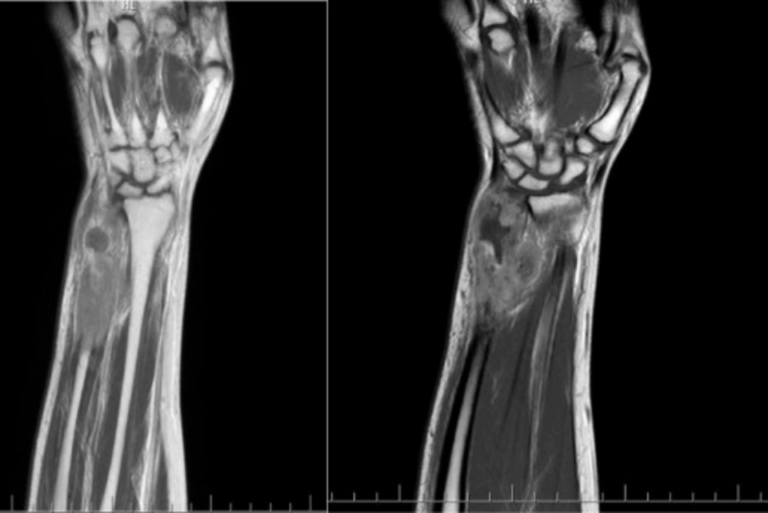

To determine if a tumor is cancerous, a physician should often consider ordering a CT scan or MRI, depending on the location of the tumor. Once the images have been evaluated by a qualified radiologist, biopsies of all tumors will often be performed and assessed by a pathologist to determine if they are benign or malignant. Even if the initial results come back benign, this type of cancer can rapidly grow, spread, or change in nature. Many years after the initial diagnosis, tumors can reoccur locally in the nearby lymph nodes or the cells may spread to other areas of the body. Therefore, patients should insist that these tests be repeated every six months and that they be continually evaluated by a qualified physician.